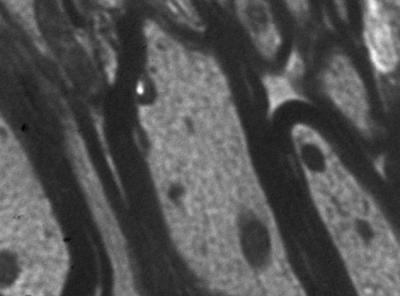

The Chinese compound Kaixin Jieyu Fang can be used to treat vascular depression; however, the underlying mechanism remains unclear. Dr. Ying Zhang and co-workers from Guang'anmen Hospital, China Academy of Chinese Medical Sciences in China This study established a rat model of chronic cerebral ischemia-caused white matter damage by ligation of the bilateral common carotid arteries. Rats received daily intragastric administration of a suspension of Kaixin Jieyu Fang powder. Kaixin Jieyu Fang was made from two prescriptions of Kaixin San and Sini San supplemented with Radix Morindae Offcinalis, consisting of eight Chinese herbs including Radix Ginseng, Radix Bupleuri, Fructus Aurantii Immaturus, Radix Morindae Officinalis, Poria, Radix Polygalae, Radix Paeoniae Rubra and Radix Glycytthizae. After treatment, the degree of white matter damage in the cerebral ischemia rat model was alleviated, Bcl-2 protein and mRNA expression in brain tissue increased, and Bax protein and mRNA expression decreased. These results, published in the Neural Regeneration Research (Vol. 9, No. 1, 2014), indicate that Kaixin Jieyu Fang can alleviate cerebral white matter damage, and the underlying mechanism is associated with regulation of Bcl-2/Bax protein and mRNA expression, which is one of possible mechanism behind the protective effect of Kaixin Jieyu Fang against vascular depression.